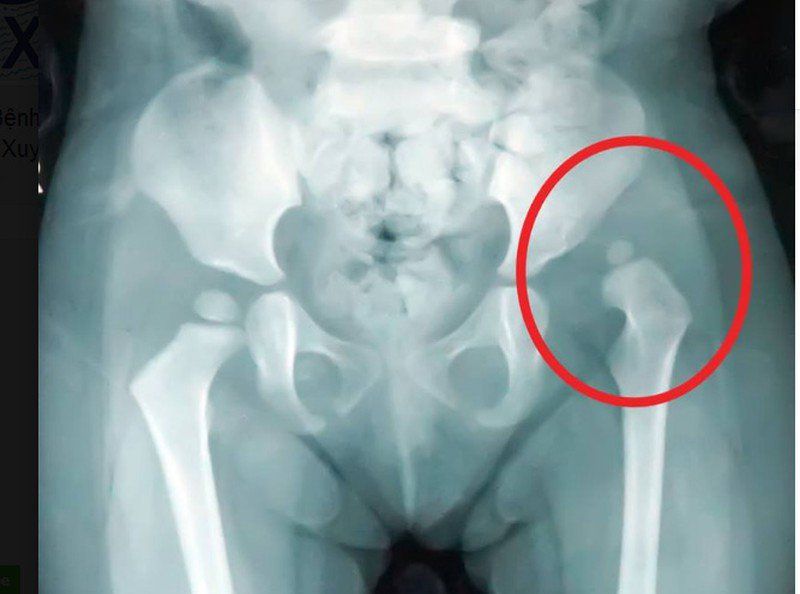

4.2 Trật khớp háng bẩm sinh và thiểu sản ổ cối ở trẻ sơ sinh

Việc xác định tình trạng trật khớp háng ở trẻ cần xác định được góc alpha và góc Beta.

- Góc alpha tạo bởi bờ cánh xương chậu và đường nối điểm đáy ổ cối với góc trên ngoài ổ cối. Góc alpha càng lớn càng tốt thường trên 70 độ.

- Góc beta: Tạo bởi đường kéo dài xương cánh chậu và đường kẻ góc trên ngoài ổ cối tiếp tuyến với chỏm xương đùi. Góc này càng hẹp càng tốt, thường nhỏ hơn 30 độ.

- Bệnh lý trật khớp háng thì nhận thấy góc beta rất lớn trên 90 độ. Tương ứng với tình trạng chỏm xương đùi không nằm bên trong ổ cối, mà nằm trên xương chậu. Khi thăm khám thấy tình trạng trật khớp háng thì cần tiến hành thăm dò động giúp đánh giá tình trạng này còn có thể điều trị bảo tồn hay không.

- Thiểu sản ổ cối: Thấy góc alpha nhỏ, ứng với việc đáy của ổ cối nông không chứa hết được chỏm xương đùi.